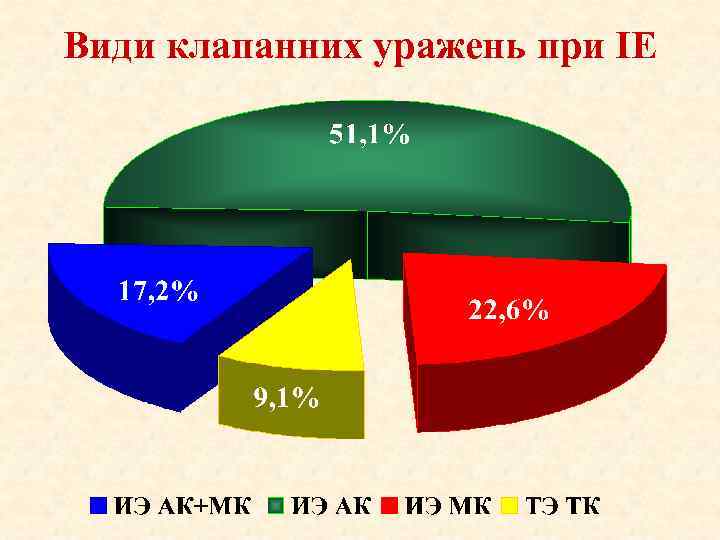

Види клапанних уражень при ІЕ